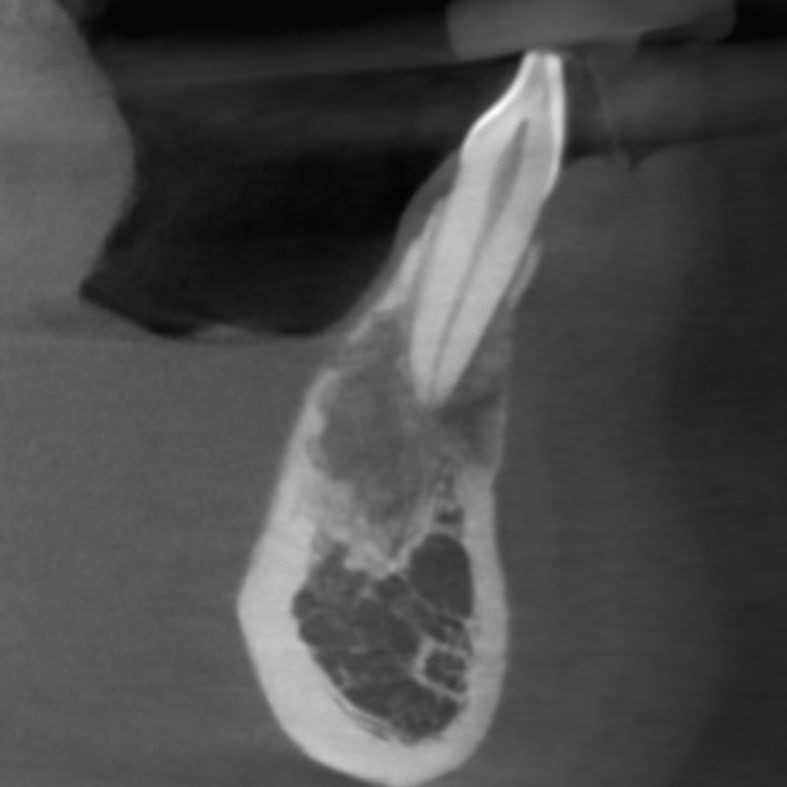

Tooth with granular radiolucency at root apex.